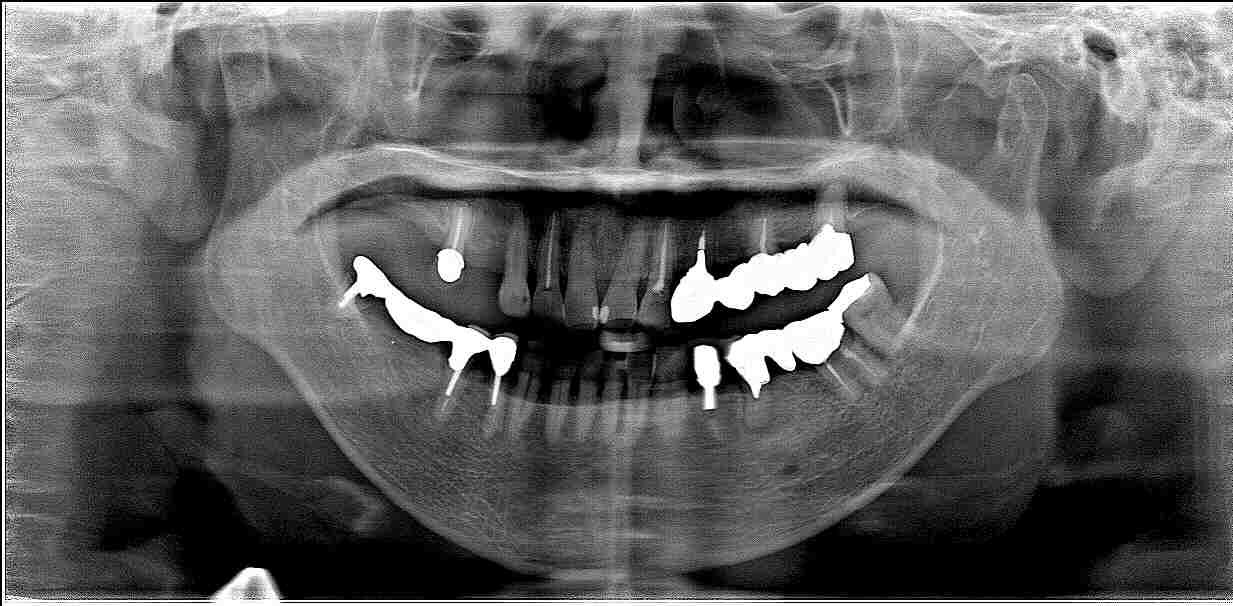

右下のインプラント埋入 インプラント埋入の実際|お知らせ |広島市安佐南区の歯科医院 右下のインプラント埋入 インプラント埋入の実際 トップ お知らせ・ブログ お知らせ 右下のインプラント埋入 インプラント埋入の実際 右下のインプラント埋入 インプラント埋入の実際 奥の歯がグラグラ ブリッジの支台歯 固いものが噛めない ブリッジを外しました ここに1本だけインプラント埋入を行っていきます 最小限で歯茎をめくります インプラントを埋入しています このように埋入しました 骨幅も狭くなり、神経に気を付けながら埋入しています 術前術後のパノラマになります 綺麗に埋入できています Web診療予約 初めての方へ 選ばれ続ける理由 院内設備について 歯が痛いしみる一般歯科 歯がぐらぐらする歯周病 健康な歯を保ちたい予防歯科 子供の虫歯予防をしたい小児歯科 銀歯をセラミックに審美歯科 白い歯を目指しませんか?ホワイトニング 矯正専門医がいるので安心矯正歯科 抜けた歯を補いたいインプラント・入れ歯 医院案内 スタッフ紹介 メリィハウス歯科クリニックオフィシャルホームページ ラベンダー歯科クリニックオフィシャルホームページ お知らせ・ブログ ホーム 診療科目 一般歯科 歯周病治療 予防治療 小児歯科 審美治療 ホワイトニング 矯正歯科 入れ歯・インプラント マウスピース矯正 初めての方へ 院長・スタッフ 設備紹介 医院案内・アクセス メニューを閉じる